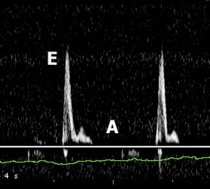

- Para valorar la función diastólica del VI se utiliza el doppler pulsado:

- Fase de protodiástole: se detecta una onda E muy prominente.

- Entra mucho flujo desde AI a VI.

- Se conoce como patrón restrictivo.

- Origina el tercer ruido

- Fase de telediástole: se contrae la AI y al final de la diástole hay un llenado que es el llenado telediastólico que con el doppler se detecta como onda A.

- Fase de protodiástole: se detecta una onda E muy prominente.

Doppler pulsado a nivel de la válvula mitral. El patrón observado es compatible con un patrón de llenado restrictivo, donde la onda E es más alta de lo normal y la onda A de menor tamaño.

- Patrón de llenado restrictivo.